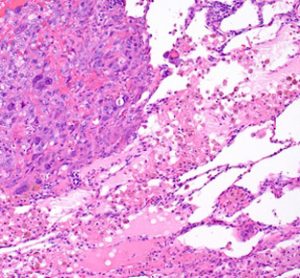

Afatinib significantly improved clinical outcomes compared to gefitinib in NSCLC trial

Results from the Phase IIb LUX-Lung 7 trial showed that afatinib significantly reduced the risk of lung cancer progression by 27% versus gefitinib...